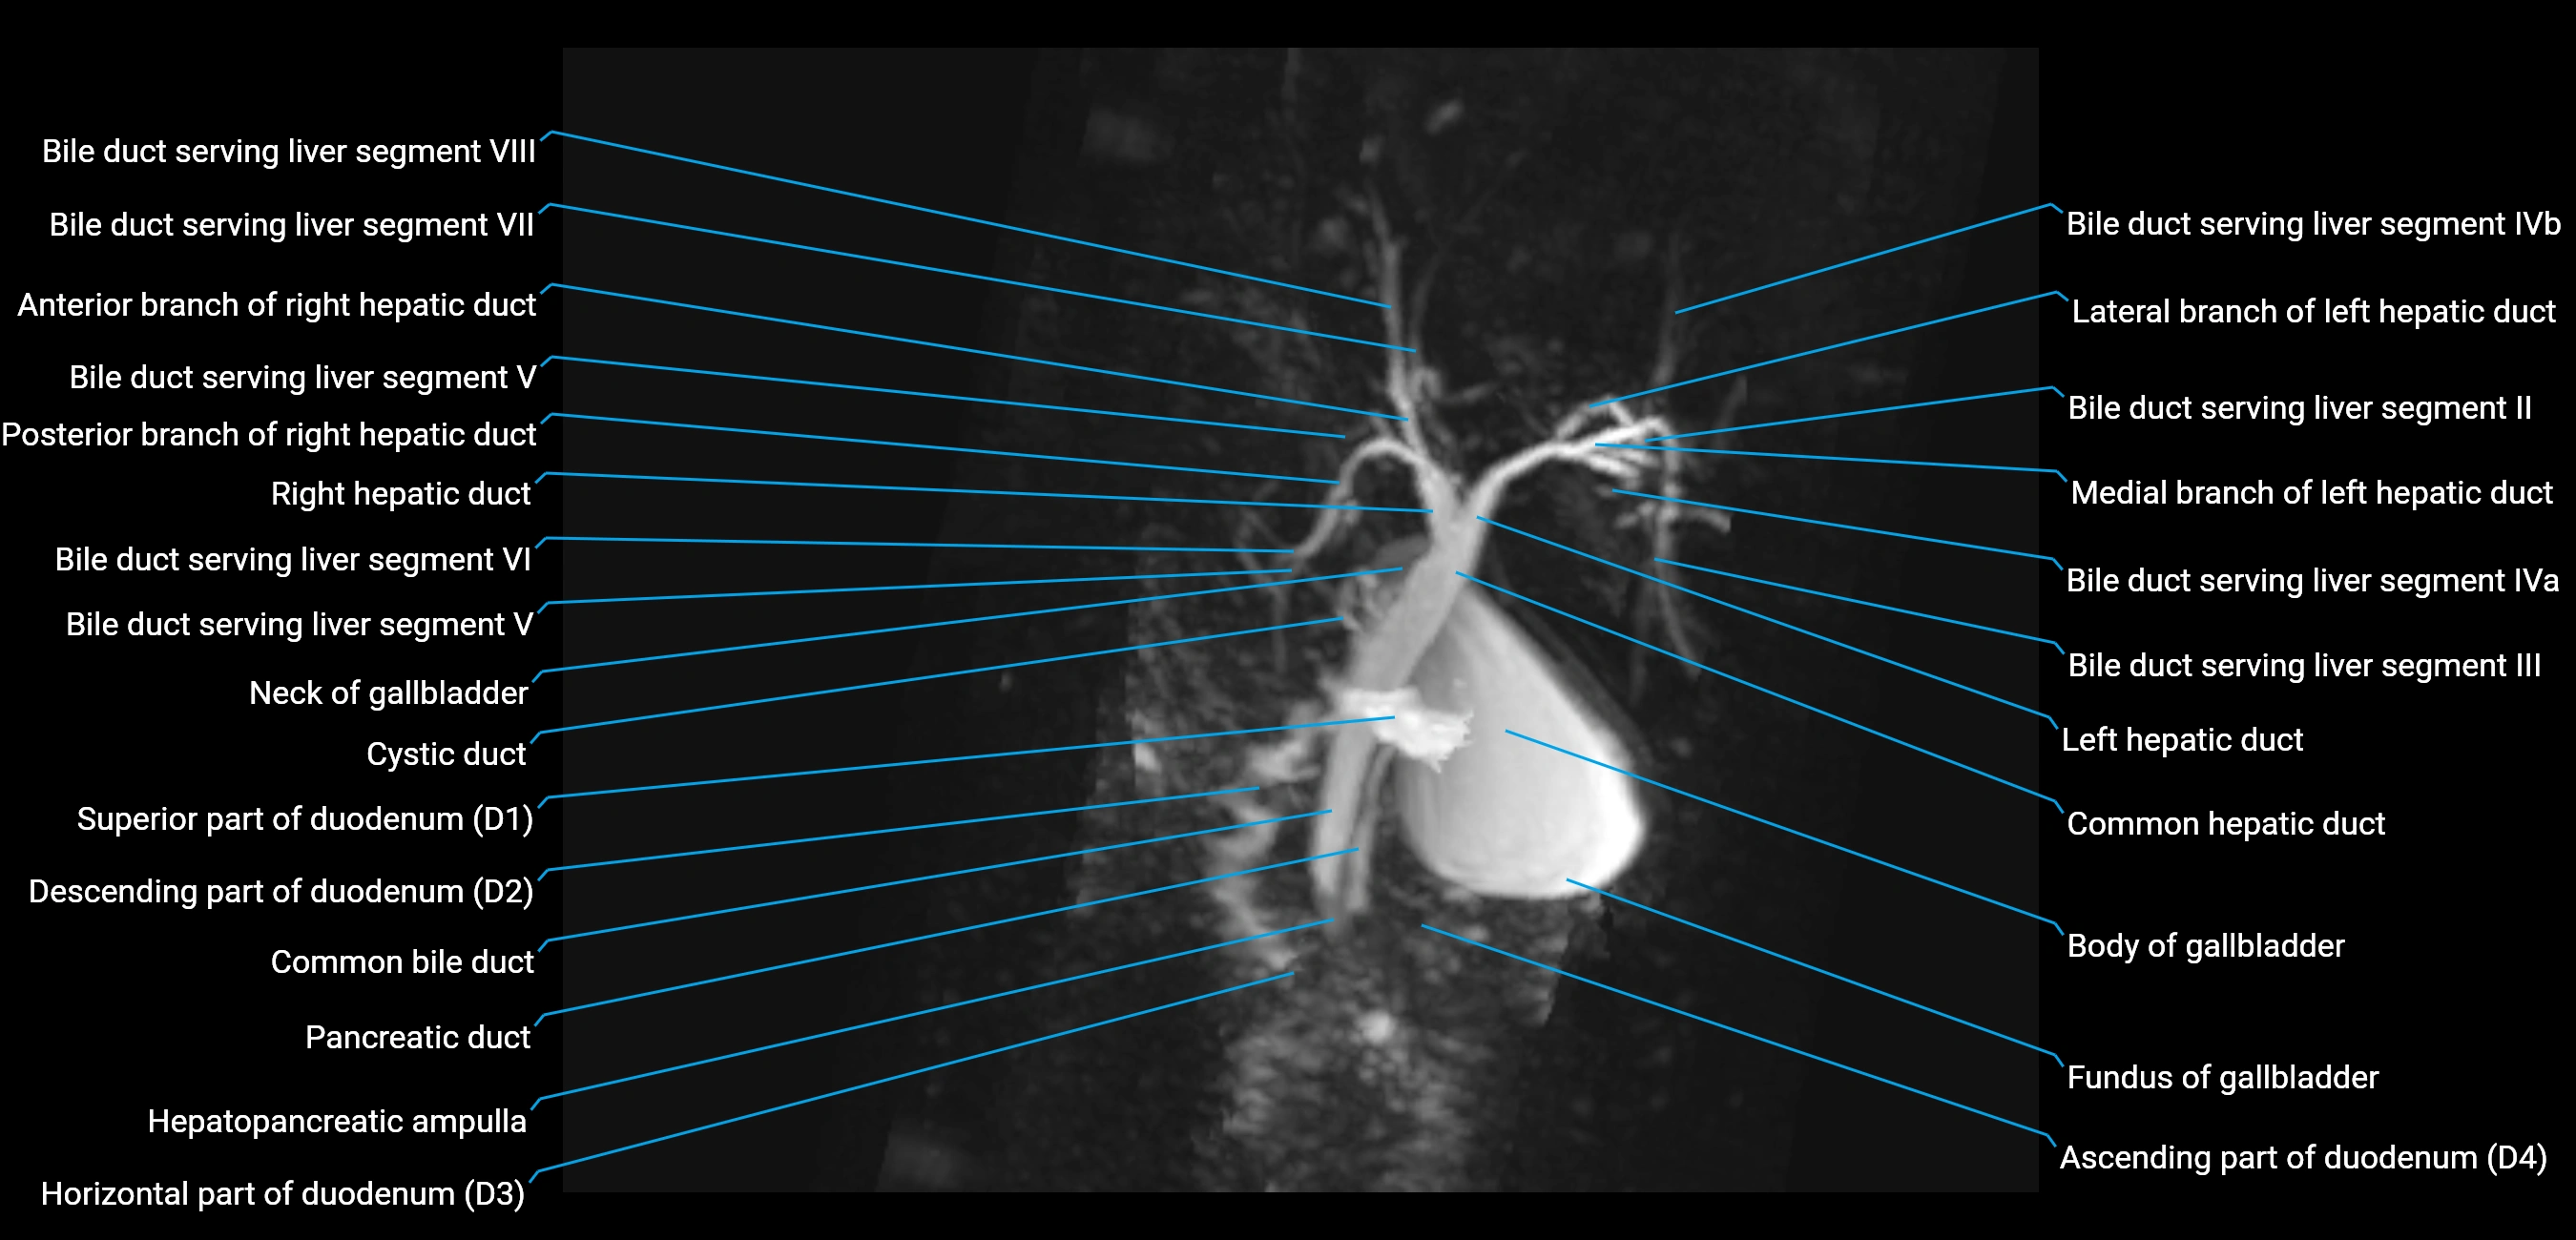

T2 TSE Fat-Saturated 3D (MRCP sequence):

• Duct visualized as a continuous bright tubular structure joining or parallel to the main pancreatic duct

• Allows 3D reconstruction of ductal anatomy and variants

• Excellent for diagnosis of pancreas divisum

Thick-slab T2 Fat-Saturated HASTE:

• Shows the accessory duct as part of the biliary–pancreatic system in a projectional image

• Highlights communication with main pancreatic duct and opening into the minor papilla

• Filling defects (stones, strictures) seen as dark spots within bright fluid

MRI image

image

Fullscreen Image